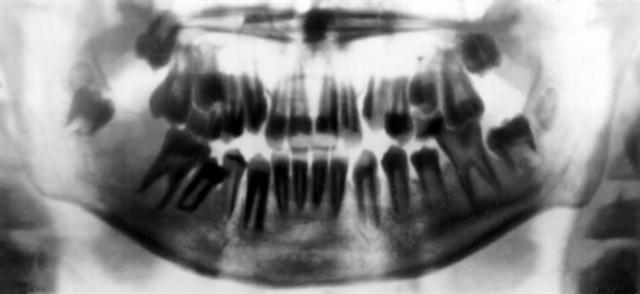

Рис. 1. Пантомограмма верхней и нижней челюстей.